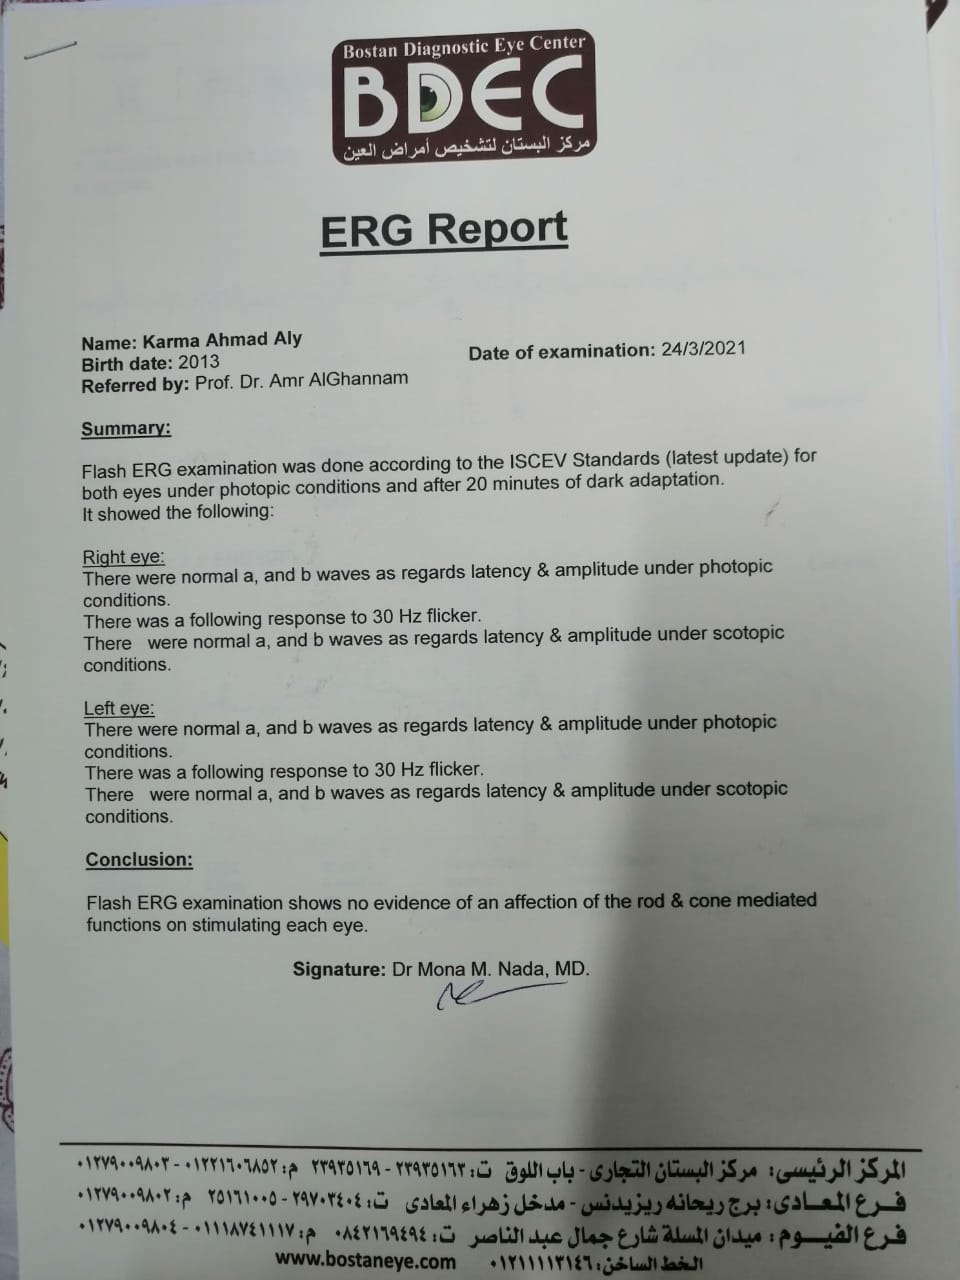

وأشار إلى أنه بعد خروج كارما من المستشفى تم إجراء فحوصات أخرى عليها، تبينت عدم التطابق بين التقارير الطبية لها بداخل المستشفى والفحوصات الجديدة.

وقال علي: "بنتي جالها ضمور في المخ وفي كل الحواس، بسبب الدوا الغلط، بنعملها علاج طبيعي بيتكلف في الشهر 20 ألف جنيه"، مشددًا": "هي بتفتح عينها بس".